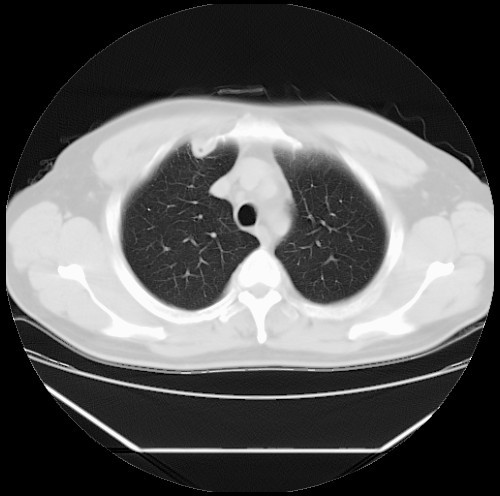

标题: CT22085:双肺多发结节

男,44岁,咳嗽,痰中带血2天。

病灶大部分位于胸膜下,结节大小相差不是很大,肺尖太干净。这种结核没见过,我认为可排除。

首先考虑转移,不除外肉芽肿、真菌感染。建议查其它。

除肺内及胸膜下可见多发大结节外,在肺小叶中心核、小叶间隔及支气管血管束上亦可见多方小结节,可以认为是随机分布。考虑转移可能性大。

仔细观察病灶形态,病灶边界部分清楚,结合临床症状,首先考虑转移,纵隔内多个肿大淋巴结影。

双肺血管纹理末端多发类圆形结节,边界光滑清晰 气管前腔静脉后淋巴结肿大

考虑转移瘤

本例双肺多发类圆形高密度灶,边清,结合病史多考虑双肺多发转移改变,可以结合实验室检查。